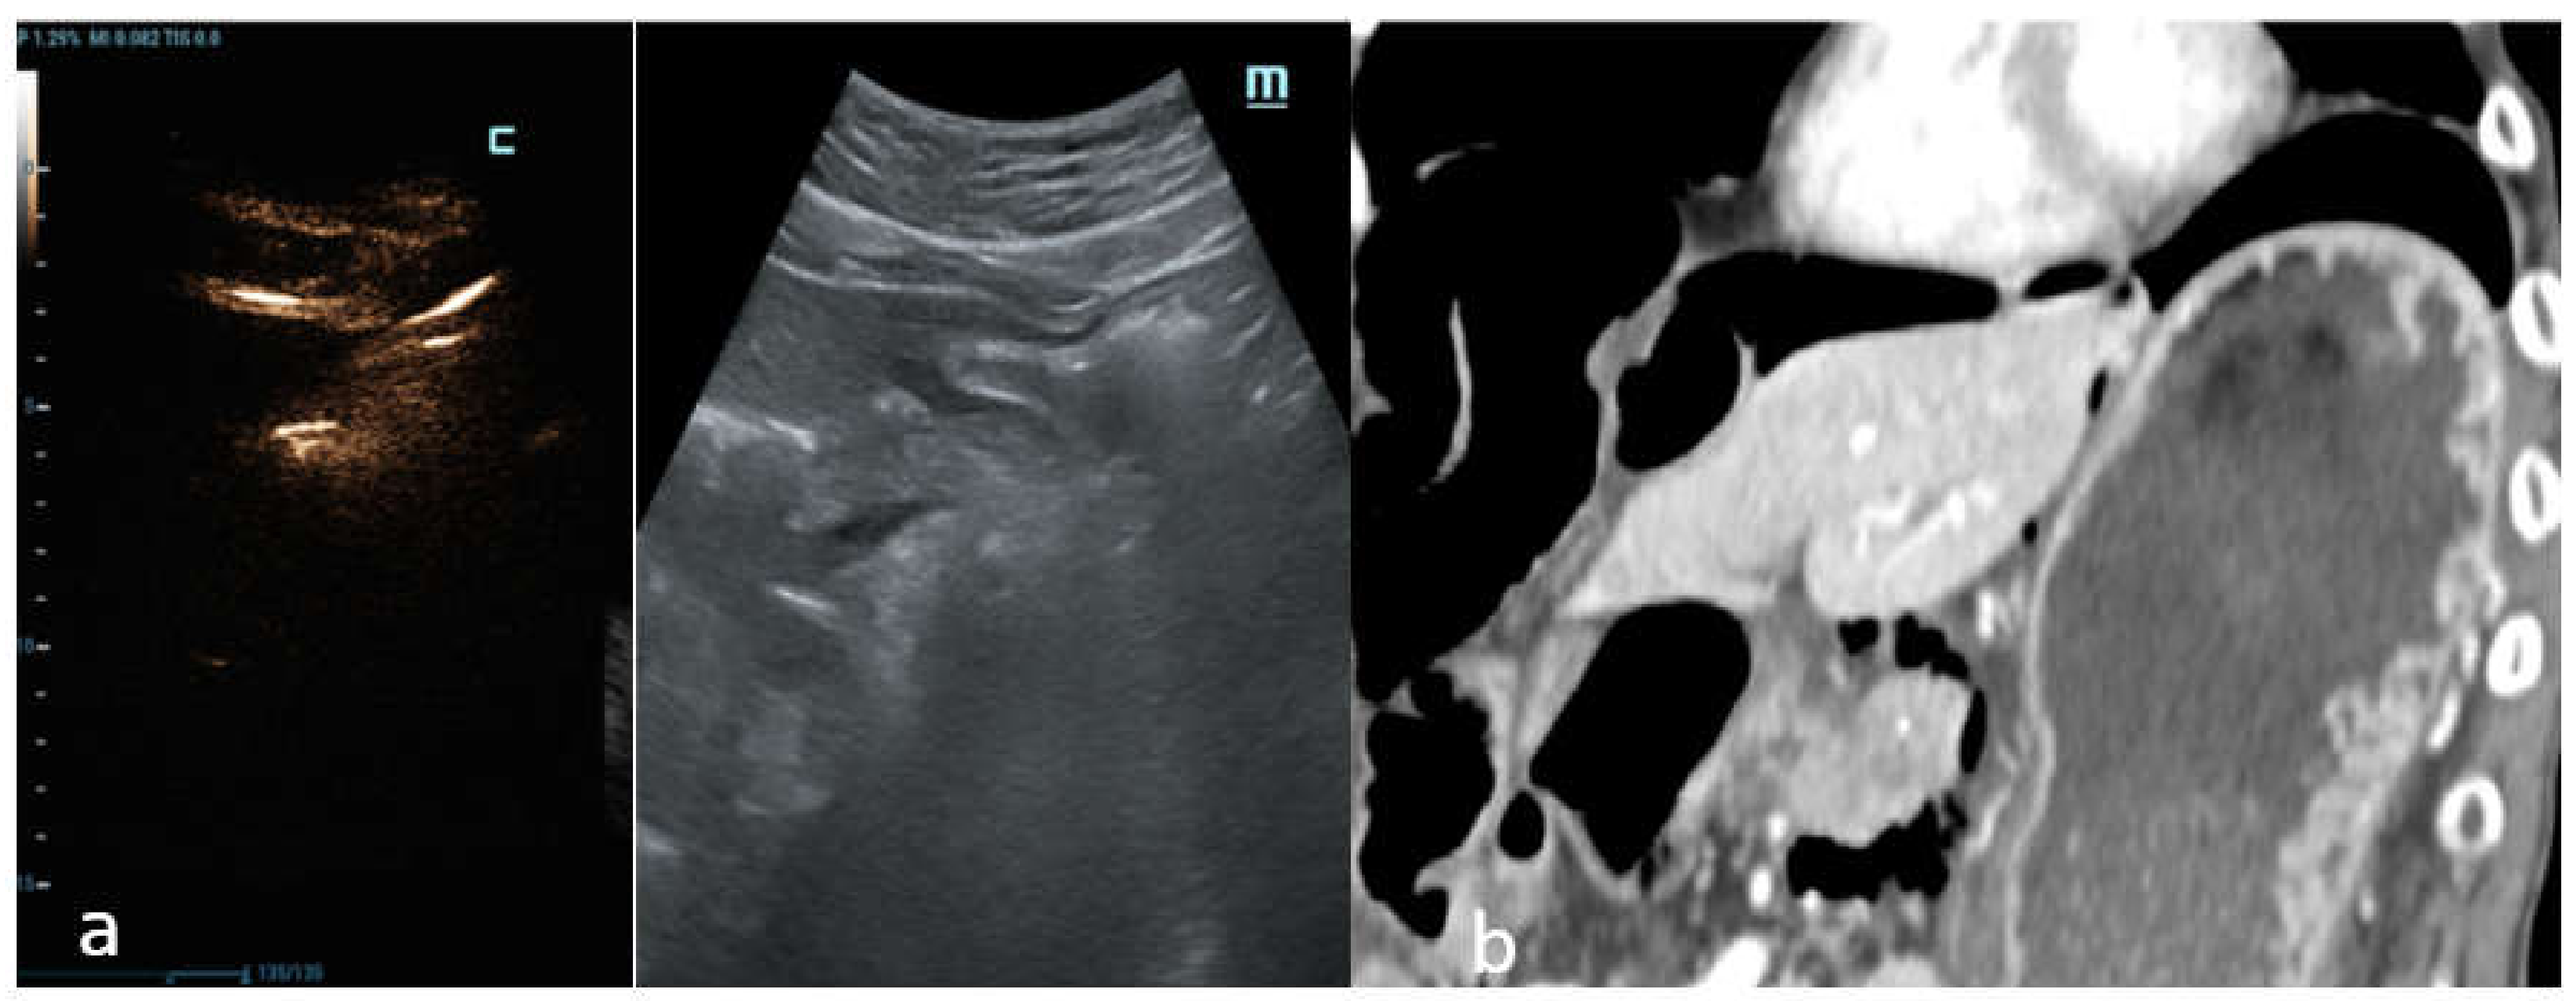

C-mode gave a more intense appearance to the peritoneal stripe when compared to B-mode, identifying the amount of free air, similar to the strongly enhanced peritoneal lines in the pre-hepatic space (

Figure 3), and better enounced the presence of intensely enhanced small amounts of air around the falciform ligament (

Figure 4a), as confirmed by the CT scan (

Figure 4b).

In another case, C-mode was able to detect free abdominal air around the duodenum and the pancreatic head with certainty (

Figure 6a), which was also displayed perfectly by the CT scan (

Figure 6b).